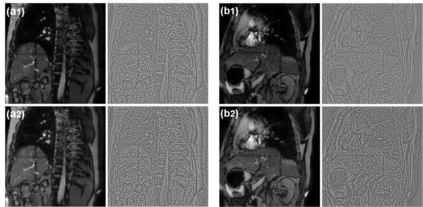

Objective:To develop a no-reference image quality assessment method using automated distortion recognition to boost MRI-guided radiotherapy precision.Methods:We analyzed 106,000 MR images from 10 patients with liver metastasis,captured with the Elekta Unity MR-LINAC.Our No-Reference Quality Assessment Model includes:1)image preprocessing to enhance visibility of key diagnostic features;2)feature extraction and directional analysis using MSCN coefficients across four directions to capture textural attributes and gradients,vital for identifying image features and potential distortions;3)integrative Quality Index(QI)calculation,which integrates features via AGGD parameter estimation and K-means clustering.The QI,based on a weighted MAD computation of directional scores,provides a comprehensive image quality measure,robust against outliers.LOO-CV assessed model generalizability and performance.Tumor tracking algorithm performance was compared with and without preprocessing to verify tracking accuracy enhancements.Results:Preprocessing significantly improved image quality,with the QI showing substantial positive changes and surpassing other metrics.After normalization,the QI's average value was 79.6 times higher than CNR,indicating improved image definition and contrast.It also showed higher sensitivity in detail recognition with average values 6.5 times and 1.7 times higher than Tenengrad gradient and entropy.The tumor tracking algorithm confirmed significant tracking accuracy improvements with preprocessed images,validating preprocessing effectiveness.Conclusions:This study introduces a novel no-reference image quality evaluation method based on automated distortion recognition,offering a new quality control tool for MRIgRT tumor tracking.It enhances clinical application accuracy and facilitates medical image quality assessment standardization, with significant clinical and research value.